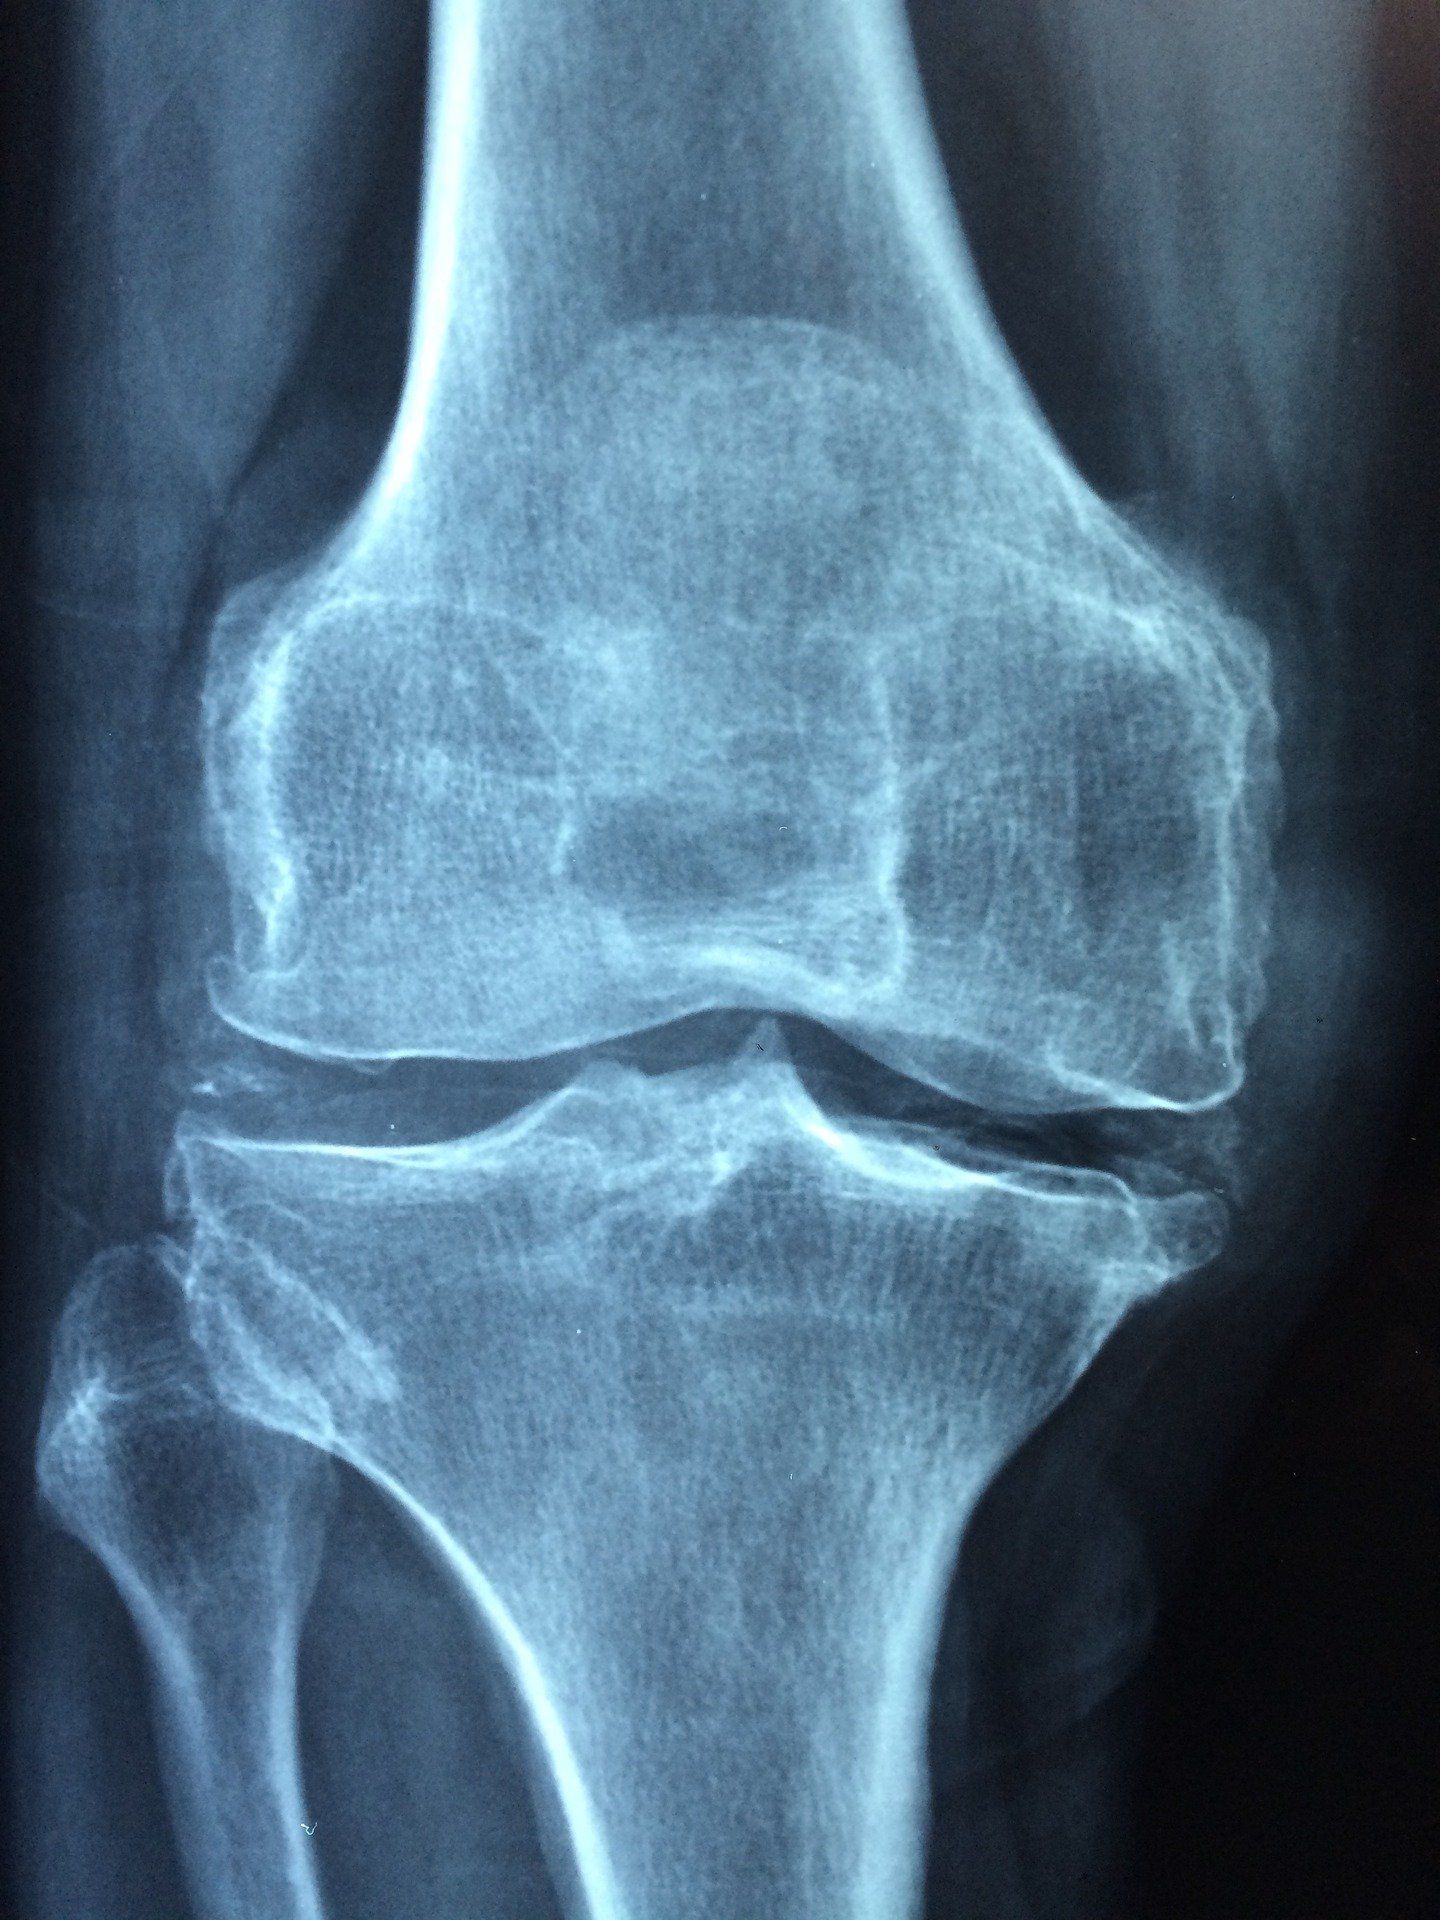

Need a new avenue to treat your pain? Elko Spine is proud to offer Platelet-Rich Plasma Therapy (PRP), a cutting-edge treatment that uses a patient’s own healing system to repair connective tissues, such as muscles, ligaments, joints, and injured tendons. It involves injecting a patient with a concentration of their own blood platelets. This regenerative therapy has been successful in treating a number of injuries and conditions, such as ACL injuries, rotator cuff tears, plantar fasciitis, hamstring muscle injuries, and arthritis.